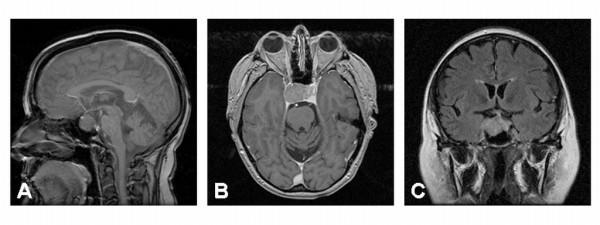

Here, we report the case of a fatal pituitary carcinoma evolving within two years from an adrenocorticotrophic hormone (ACTH)-secreting macroadenoma and review the global literature regarding this rare neuroendocrine tumor.

在此,我们报告一例致命性垂体癌病例,该病例在两年内由分泌促肾上腺皮质激素(ACTH)的大腺瘤演变而来,并回顾了关于这种罕见神经内分泌肿瘤的全球文献。